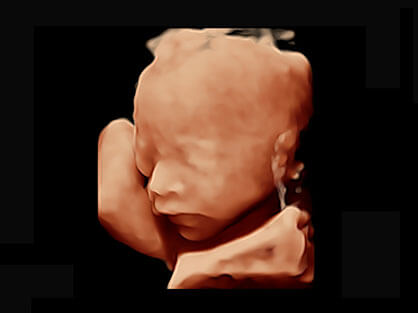

体贴入微 关爱妇产

• M-Slice多切面成像

0.5mm厚度的薄层切片显像,可清晰显示微小病灶的连续断面。

• S-Live Silhouette光影成像

可同时显示组织结构表面和内部的轮廓信息,达到透视效果,为临床提供更丰富的诊断信息。

• 产科自动测量

自动获取标准切面,自动完成测量,帮助医生快速完成检查,同时提升测量准确性。

• 丰富的探头配置

宽频带腹部凸阵探头和腹部容积探头、大角度腔内探头和腔内容积探头、独特的生殖专用曲柄探头,为妇产应用提供全面诊疗方案。